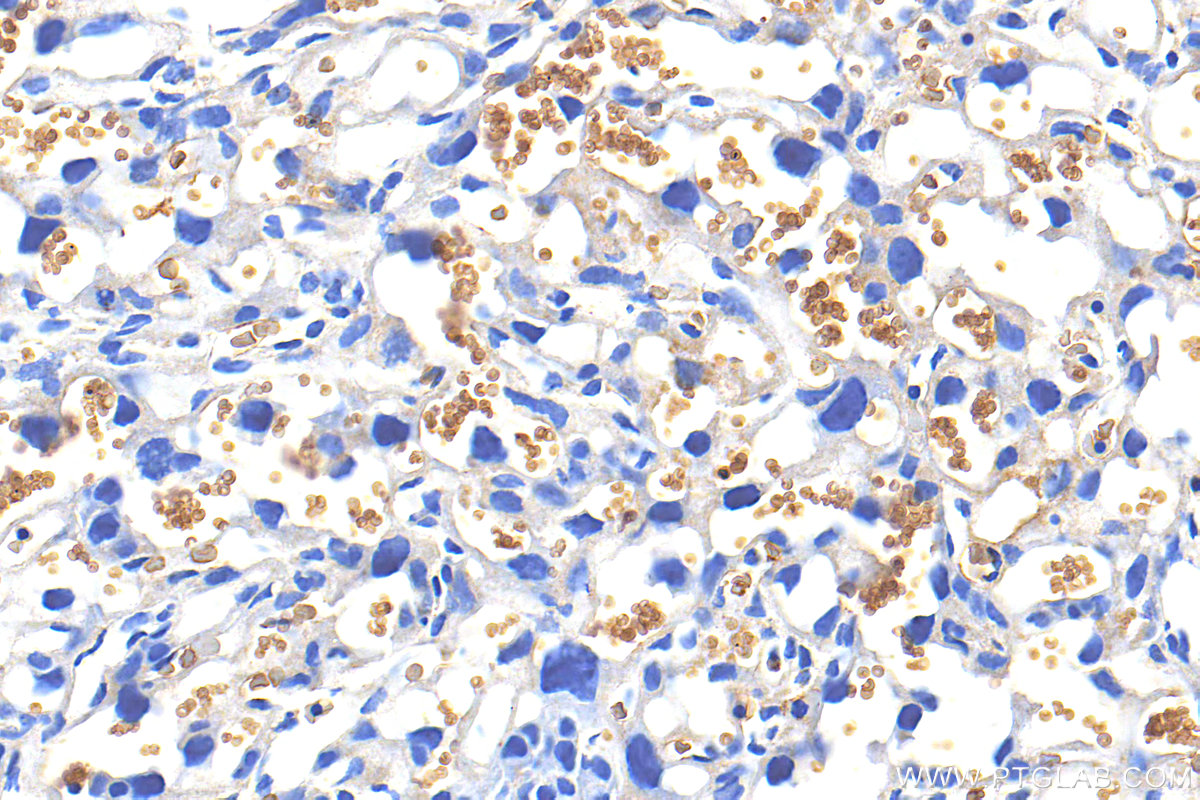

| Positive IHC detected in | mouse placenta tissue Note: suggested antigen retrieval with TE buffer pH 9.0; (*) Alternatively, antigen retrieval may be performed with citrate buffer pH 6.0 |

32339-1-AP targets Glycophorin A/CD235a in IHC, ELISA applications and shows reactivity with mouse samples.